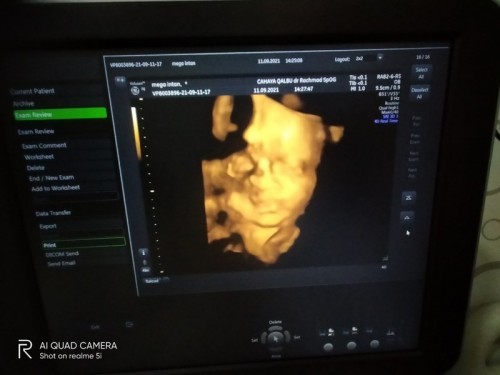

Bunda2, mau tanya nih, apakah wajar usia kehamilan 28minggu (7bulan) posisi bayinya sungsang?😔

Jenis kelamin perempuan

sama aku juga baru aja USG usia 28 minggu, malah ari2 nya dibawah nutup jalan lahir, siutun masih diatas kepalanya... tp kta dokter masih ada kemungkinan muter posisinya... krn masih 7 bulan... bismillah smga smua baik2 aja...